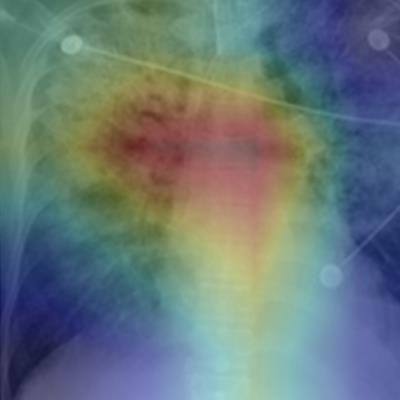

MIT's machine-learning algorithm quantifies edema on chest x-rays on a scale from 0 (normal) to 3 (alveolar edema). Image courtesy of MIT CSAIL.

MIT's machine-learning algorithm quantifies edema on chest x-rays on a scale from 0 (normal) to 3 (alveolar edema). Image courtesy of MIT CSAIL."The joint image-text representation learning framework incorporates the rich information present in the free-text radiology reports and significantly improves the performance of edema assessment compared to learning from images alone," the authors wrote in their article, published online recently in arXiv.org. "Moreover, our experimental results show that joint representation learning benefits from the large amount of unlabeled image-text data."

Their model also shows the parts of the image and report that corresponded to its prediction. They then assessed the performance of several variants of their model, including one trained using only the labeled images and another trained using both the labeled images and unlabeled images and reports. Performance was compared with classifications of edema levels made by expert radiologists on the test set.